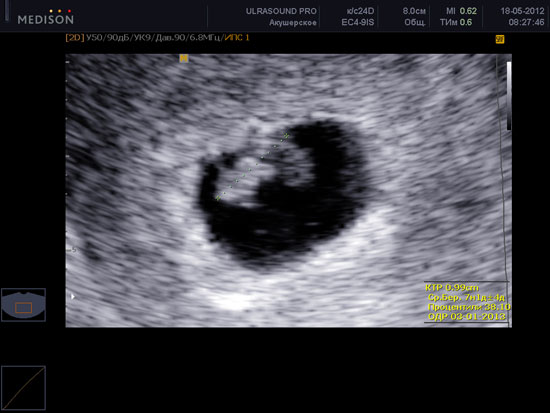

Начинается подразделение сердца эмбриона на камеры. Сейчас оно бьется со скоростью 100-160 ударов в минуту, позволяя крови циркулировать по всему телу. Биение сердца можно заметить при проведении УЗИ на седьмой неделе беременности.

УЗИ на седьмой неделе беременности

Фото: ultraclinic.com.ua